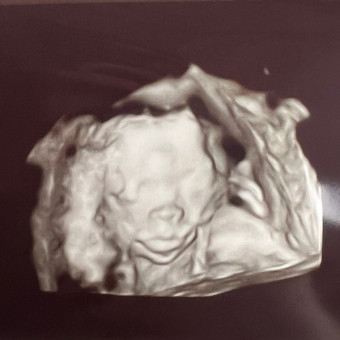

Christine's Baby Registry

Christine & Shawn DiVirgilio-Arnold

August 31, 2026